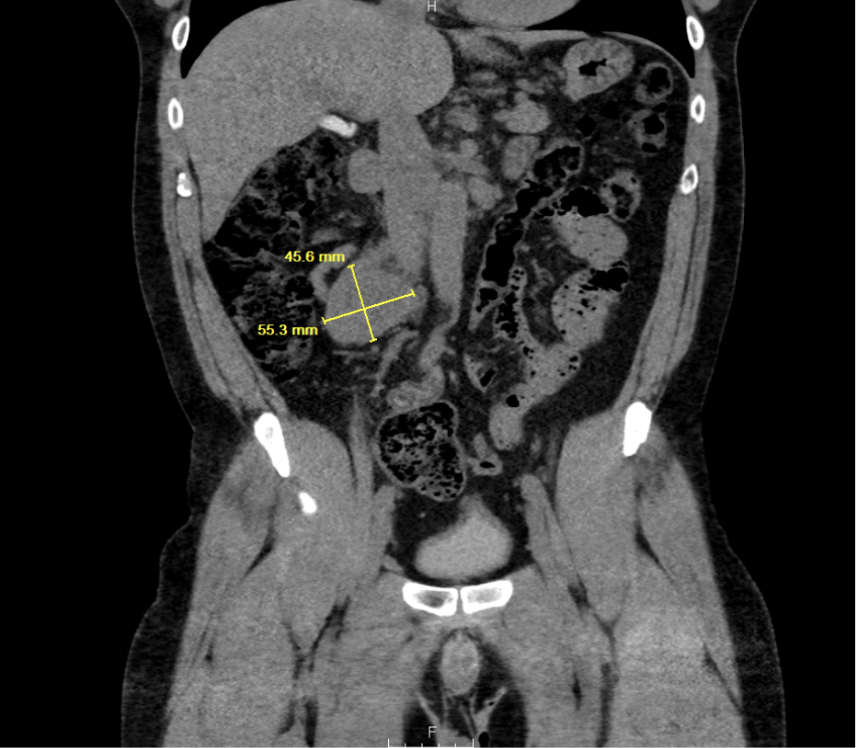

A 47-year-old African-American male with no known cardiac history presented with hypertensive emergency, acute heart failure (LVEF 30–35%), and multiorgan dysfunction. Imaging revealed a 14 cm extra-adrenal paraganglioma encasing the bilateral renal arteries, IVC, and adjacent vascular structures. Preoperative echocardiograms showed a progressive decline in LVEF from 45–50% to 30–35% over five months within diagnosis of paraganglioma. Surgical resection was performed, and histology confirmed paraganglioma. After resection, the patient continued to exhibit persistent hypertension despite adherence to antihypertensive therapy and lifestyle modification.